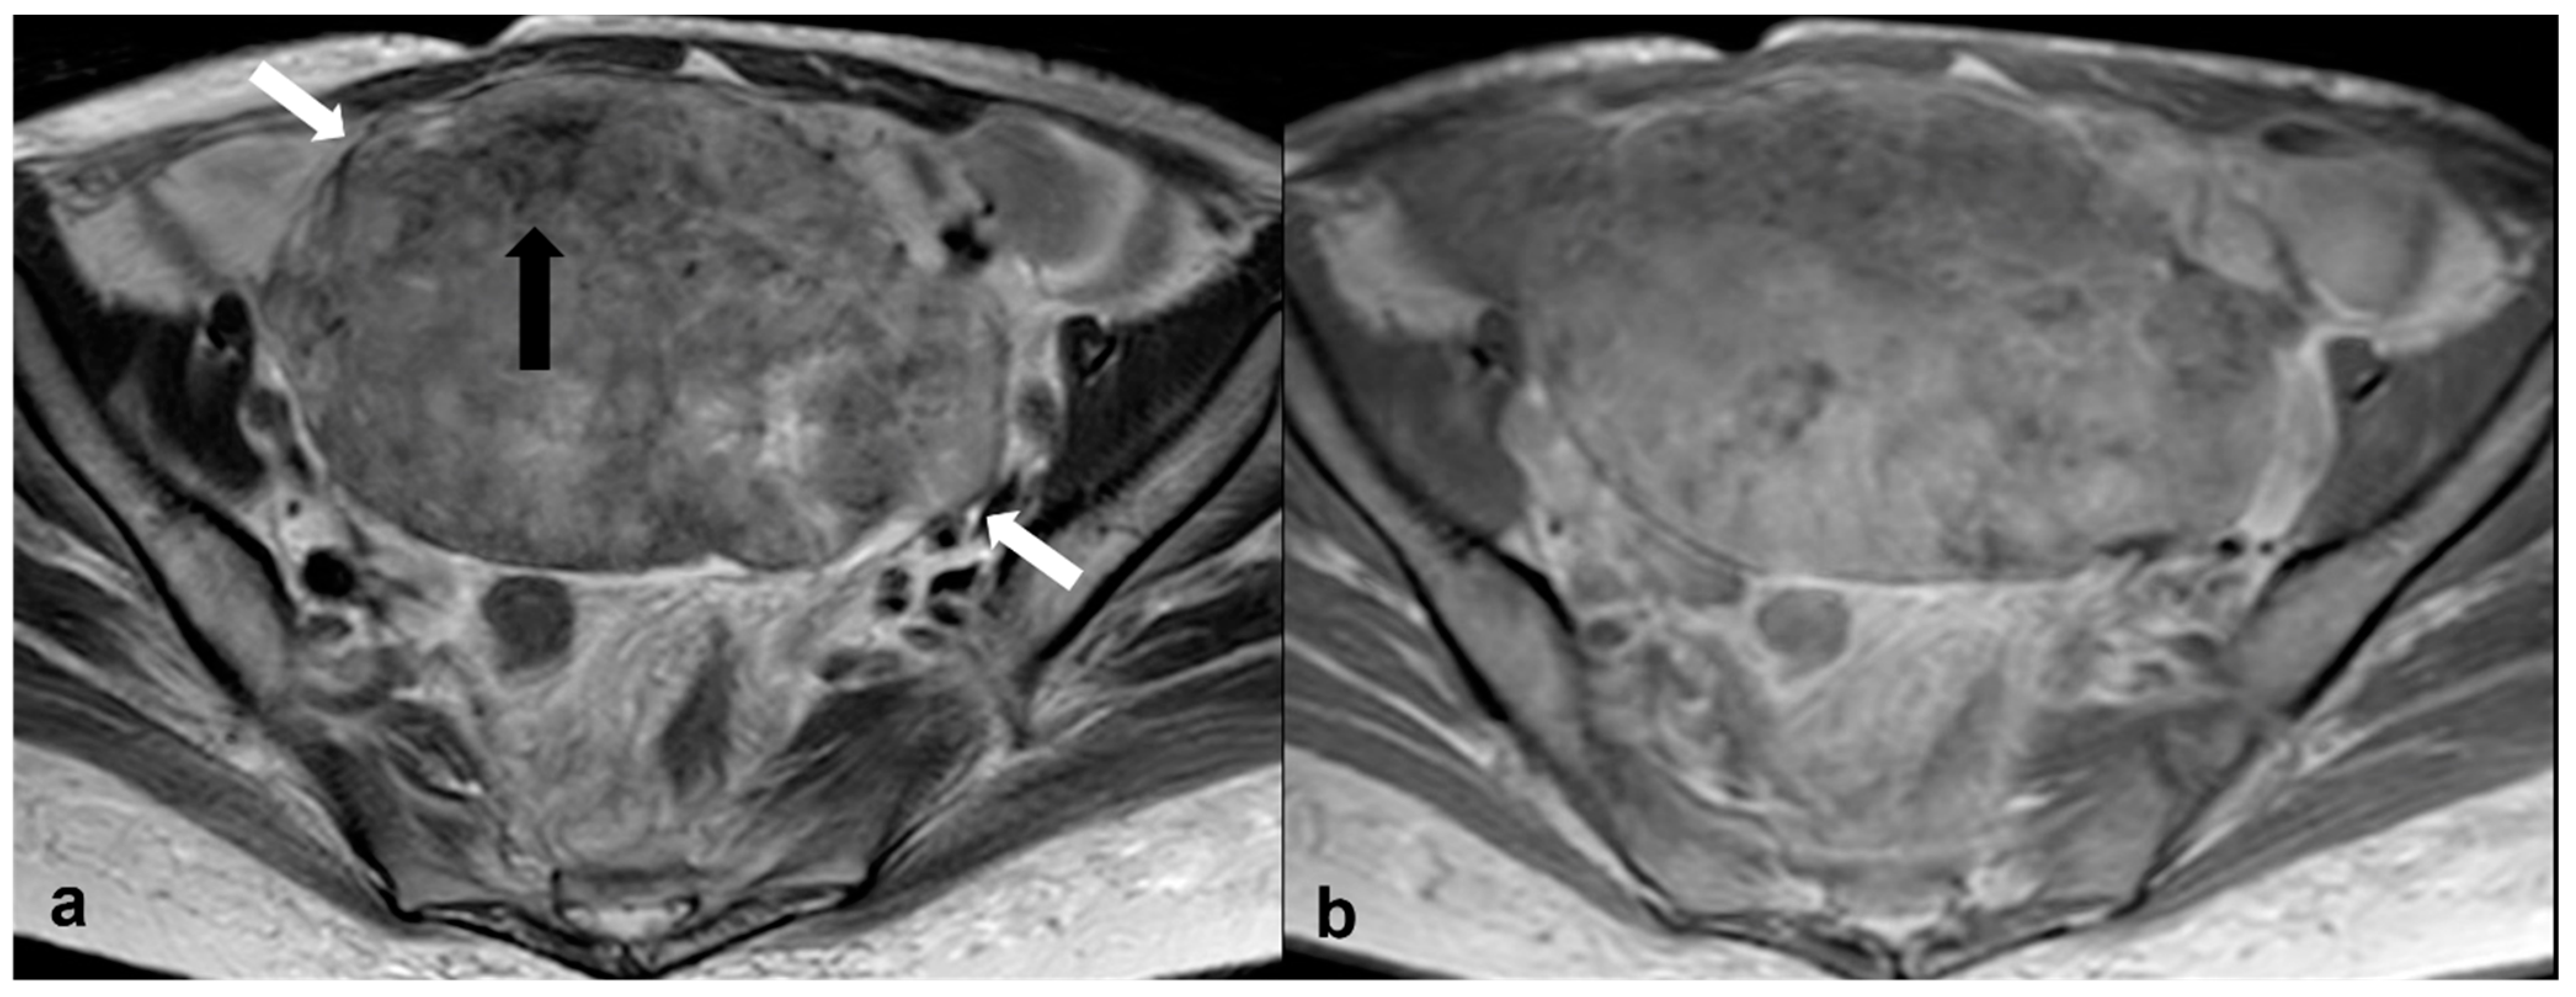

2.3.5. Metastases

2.4. Adolescence-Germ Cell Tumors